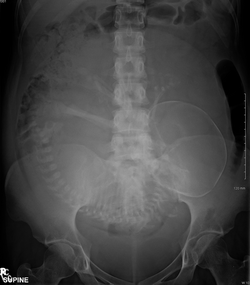

Plain abdominal Xray of a pregnant women